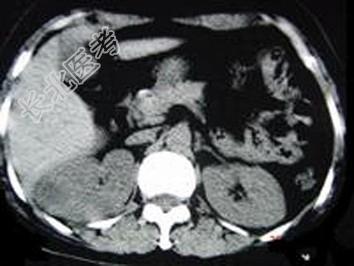

- 单项选择题女,12岁, 右腰部疼痛10天,尿检可见大量的脓细胞 CT平扫+增强如图所示, 应诊断为 ( )

A、右肾脓肿

B、右侧感染性肾囊肿

C、右肾转移瘤

D、右侧肾癌

E、右肾结核